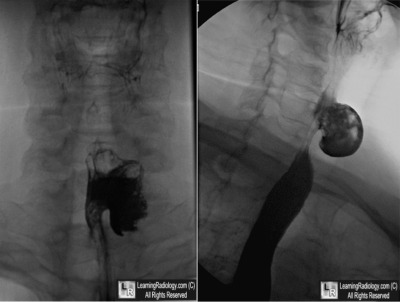

Frontal and Oblique Esophagram-Cervical Esophagus

4. Killian-Jamieson Diverticulum

Killian-Jamieson Diverticulum

- Arises from cervical esophagus below cricopharyngeal muscle (about C5-C6) laterally

- Originates on the antero-lateral wall of cervical esophagus through a muscular gap (the Killian-Jamieson space) lateral to longitudinal muscle of the esophagus

- It is a pulsion, not a true, diverticulum since it does not involve all layers of esophagus

- Usually smaller than a Zenker diverticulum